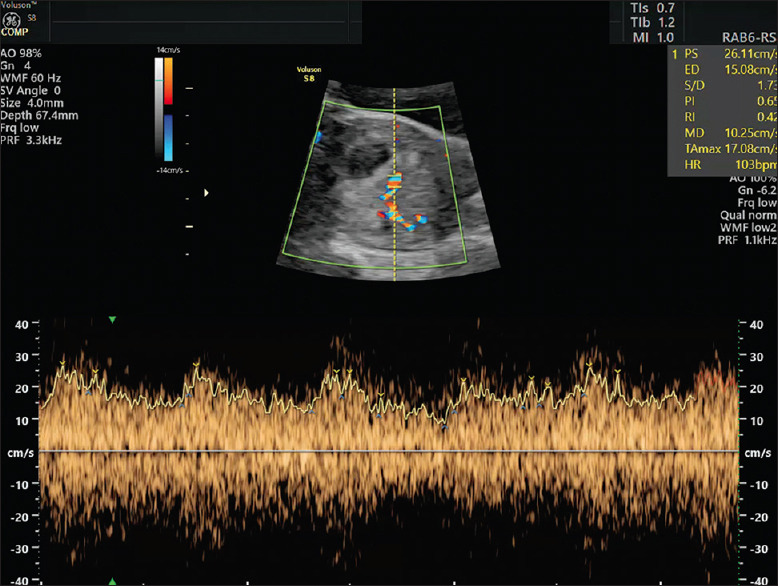

背景:复发性妊娠丢失(RPL)通常源于高凝状态,这加剧了抗磷脂综合征(APS)和血栓形成,导致早期胎盘问题。尽管使用了低分子肝素(LMWH)和低剂量阿司匹林(LDA)等治疗方法,但结果各不相同。本研究建议使用妊娠早期多普勒超声-特别是8周时子宫桡动脉阻力指数(URa-RI)和11-13周时伴有舒张前缺口(Ut-notch)的子宫动脉搏动指数(Ut-PI) -来更好地预测妊娠成功并降低不良后果的风险。目的:本研究的目的是评估URa-RI、Ut-PI和Ut-notch在成功妊娠和不成功妊娠、有不良事件妊娠和无不良事件妊娠之间的差异。环境和设计:该研究在临床环境中进行,采用回顾性队列设计,样本为72例有两次或两次以上RPL发作史的患者。材料和方法:收集8周时URa-RI和11-13周时Ut-PI和Ut-notch的数据。分析中考虑了母亲的特征,包括年龄、体重指数、流产次数、病因和免疫炎症反应。采用统计学分析:对URa-RI、Ut-PI和Ut-notch数据进行比较统计学分析,评估其与妊娠成功和不良结局的关系。对成功和不成功怀孕的变量进行统计比较,并分析不良事件。使用SPSS (IBM,第27版)进行分析。卡方检验用于名义分类和多变量logistic回归校正年龄、体重指数(BMI)、既往妊娠损失、病因和抗核抗体阳性。主要结局(URa-RI、Ut-PI和Ut-notch)以比值比和95%置信区间(ci)进行报告。结果:URa-RI较低(P < 0.0001)。不成功妊娠的URa-RI平均值(0.50±0.09比0.38±0.04,P < 0.0001)也显著高于不成功妊娠。Ut-PI高、Ut-notch阳性导致不良事件风险显著增加,分别为19.4倍、8.1倍(95% CI = 4.2 ~ 51.6、3.12 ~ 20.5,P < 0.0001)。结论:本研究证明了妊娠早期多普勒超声(URa-RI, Ut-PI和Ut-notch)在预测RPL患者妊娠成功和不良事件方面的作用,特别是那些使用低分子肝素和LDA治疗的患者。这些超声标记物可能为管理和预测与血栓形成和APS相关的RPL病例的结果提供有价值的指导。

Background: Recurrent pregnancy loss (RPL) often stems from a hypercoagulable state that exacerbates conditions such as antiphospholipid syndrome (APS) and thrombophilia, leading to early placental issues. Although treatments such as low-molecular-weight heparin (LMWH) and low-dose aspirin (LDA) are used, outcomes vary. This study proposes using first-trimester Doppler ultrasound - specifically, uterine radial artery resistance index (URa-RI) at 8 weeks and uterine artery pulsatility index (Ut-PI) with pre-diastolic notching (Ut-notch) at 11-13 weeks - to better predict successful pregnancies and reduce risks of adverse outcomes.

Materials and methods: Data on URa-RI measured at 8 weeks and Ut-PI and Ut-notch measured at 11-13 weeks were collected. Maternal characteristics - including age, BMI, number of pregnancy losses, etiopathology and immuno-inflammatory response - were considered in the analysis.

Results: Low URa-RI (<0.45) at 8 weeks gives a 16.4 times higher chance for the management to be successful and result in a healthy take-home baby (95% CI = 4.4-61, P < 0.0001). The mean URa-RI was also significantly higher in unsuccessful pregnancy (0.50 ± 0.09 vs. 0.38 ± 0.04, P < 0.0001). High Ut-PI and positive Ut-notch result in a significant increase of adverse event risk, which are 19.4 times and 8.1 times, respectively (95% CI = 4.2-51.6 and 3.12-20.5, P < 0.0001).